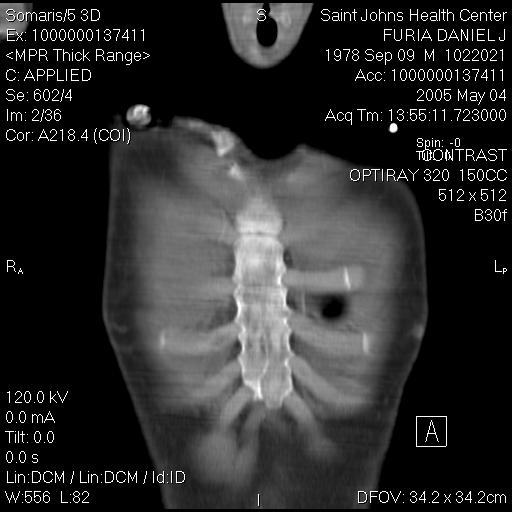

"Blebs" are weak spots that form at the top of the lung. These weak spots can leak air and cause a lung to collapse. This image shows dozens of small blebs on each of my lungs. This cat scan image was taken from above, looking down on to the top of the lung. (In other words try to imagine that you are floating up above me, looking down at the top of my head. If you could see layer by layer into my body, like the CT scan, you would then eventually see the tops of my lungs). The big dark black circle in the middle of the image is my windpipe.